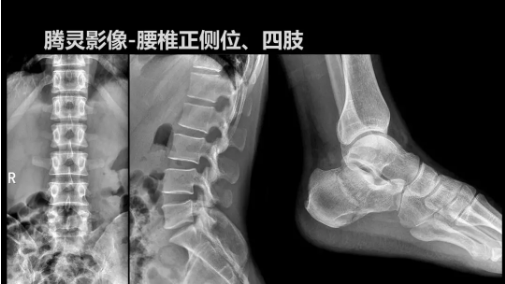

2019年10月19日,82屆秋季CMEF于青島世博城國際展覽中心如期舉辦,國內(nèi)動(dòng)態(tài)DR領(lǐng)域的佼佼者安健科技攜新品——“騰靈”多功能診斷專用動(dòng)態(tài)DR亮相展會(huì)現(xiàn)場。

“騰靈”是安健科技的第四代動(dòng)態(tài)DR產(chǎn)品,可實(shí)現(xiàn)全科室應(yīng)用。如各類常規(guī)的X線檢查、消化道檢查、骨科檢查、婦科、兒科檢查等。此外,安健科技為“騰靈”在真正意義上實(shí)現(xiàn)多科室、多功能診斷進(jìn)行了多項(xiàng)針對性設(shè)計(jì)。

相較前代產(chǎn)品,“騰靈”在圖像質(zhì)量方面得到了全面升級,“騰靈”采用17*17非晶硅平板探測器設(shè)計(jì),采集矩陣達(dá)3072*3072,動(dòng)態(tài)范圍達(dá)16bit,為成像提供超大視野的同時(shí)保證成像質(zhì)量,此外,該款機(jī)型可根據(jù)醫(yī)療機(jī)構(gòu)的差異化需求而選配不同的動(dòng)態(tài)平板探測器,以此來適應(yīng)不同階層用戶所需。